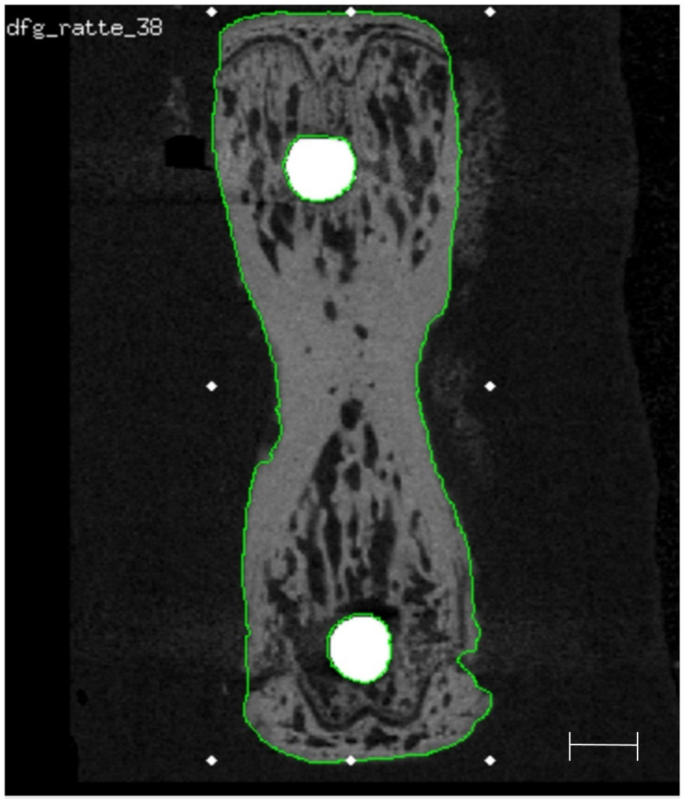

Image processing and registration

Dedicated software, i.e. the Image Processing Language (IPL) as well as the programs uct_evaluation and uct_3d (all from Scanco Medical AG, Brüttisellen, Switzerland), were employed for image processing. The periosteal contour was detected automatically32 and used to identify the outer boundaries of the vertebra.

All T0 scans were rotated such that the implants corresponded to the z-axis (Fig. 5). In all cases this alignment was performed for both implants separately, resulting in two datasets for T0, being one co-registered to the proximal and one co-registered to the distal OMI. Thereafter, T1 scans were registered with the T0 reference. During image registration, the region of the implants was excluded as they were only contained in the T0 scans. A Gaussian filter was applied to all images using 0.8 voxel as sigma and 1 voxel as support33. Segmentation of the implants and bone was performed by means of thresholds, i.e. 85% and 29% of the possible maximum grey value from all scans, respectively. Furthermore, for implant segmentation, component labelling was employed to remove residual objects other than the implants.

Representative image of a 2D transverse slice of a rat vertebra with implants in situ and the respective VOI used for the registration process (green contour), which excludes the implants (white) and defines the cortical layer and trabecular bone for accurate superimposition of the bone tissue. Scale bar equal to 1 mm.